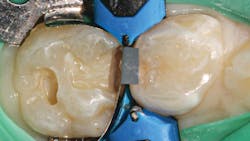

Once preparation and removal of the infected dentin is achieved, a sectional matrix and ring system (Composi-Tight 3D XR, Garrison Dental Solutions) is used. Taking particular care at the gingival margin, proper matrix placement will ensure control over leakage and any possible contamination, which is important for long-term success (figure 2).